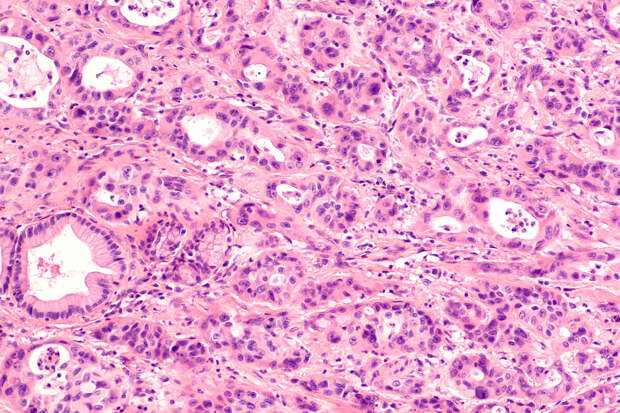

Израильским ученым удалось выяснить, что у пациентов с сахарным диабетом второго типа, принимающих агонисты рецептора GLP-1, риск развития рака поджелудочной железы не выше, чем у тех, кто использует только инсулин. Такие результаты были получены в ходе исследования с участием 543595 человек с диабетом и избыточным весом.

Сначала ученые собрали информацию о состоянии здоровья испытуемых, а затем приступили к наблюдению за ними. За 9 лет у 1665 человек развился рак поджелудочной железы. При этом заболеваемость при инсулинотерапии и применении агонистов рецепторов GLP-1 была сходной.